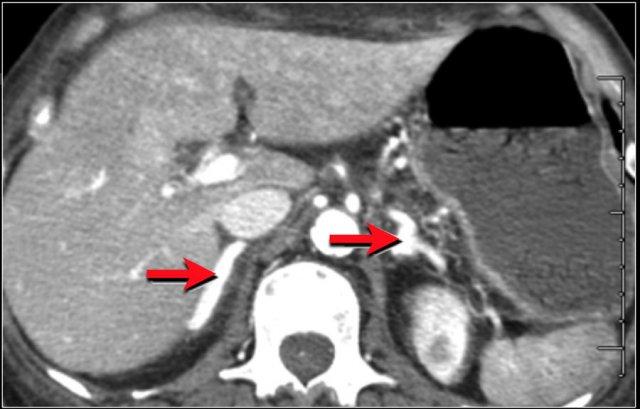

Ruột Sốc

Ở bệnh nhân sốc giảm thể tích, có sự phân phối lại dòng máu.

Điều này có thể dẫn đến hình ảnh ngấm thuốc mạnh bất thường của thành ruột, như trong trường hợp bệnh nhân đang trong tình trạng sốc mất máu này.

Lưu ý một số quai ruột có kiểu hình tăng tỷ trọng (dạng trắng), trong khi các quai khác lại có dấu hiệu bia nước.

Hình ảnh tĩnh mạch chủ dưới dạng khe hẹp là do tình trạng giảm thể tích tuần hoàn (mũi tên đỏ).

Do hệ quả của sự phân phối lại dòng máu ưu tiên đến các cơ quan thiết yếu, những bệnh nhân này có thể có hình ảnh tuyến thượng thận ngấm thuốc quá mức, vì các cơ quan này cần tăng cường sản xuất adrenaline để đáp ứng với tình trạng sốc.